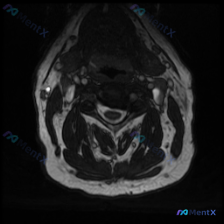

这是一份颈部MRI T2序列轴位图像,整体信噪比和对比度都不错,没有明显伪影,定位在颈椎中下段水平(约C4-C5或C5-C6)。

异常出现在患者右侧颈部浅表软组织(皮下/浅表肌肉层),具体特征:

- 信号:T2序列呈显著高信号,亮度接近甚至超过脑脊液

- 形态:类圆形,边界非常清晰

- 周围改变:没有弥漫性水肿或浸润性改变

- 对周围结构影响:病变局限在浅表,没有压迫推移深部颈椎、脊髓、血管或气道,软组织间隙保持完整